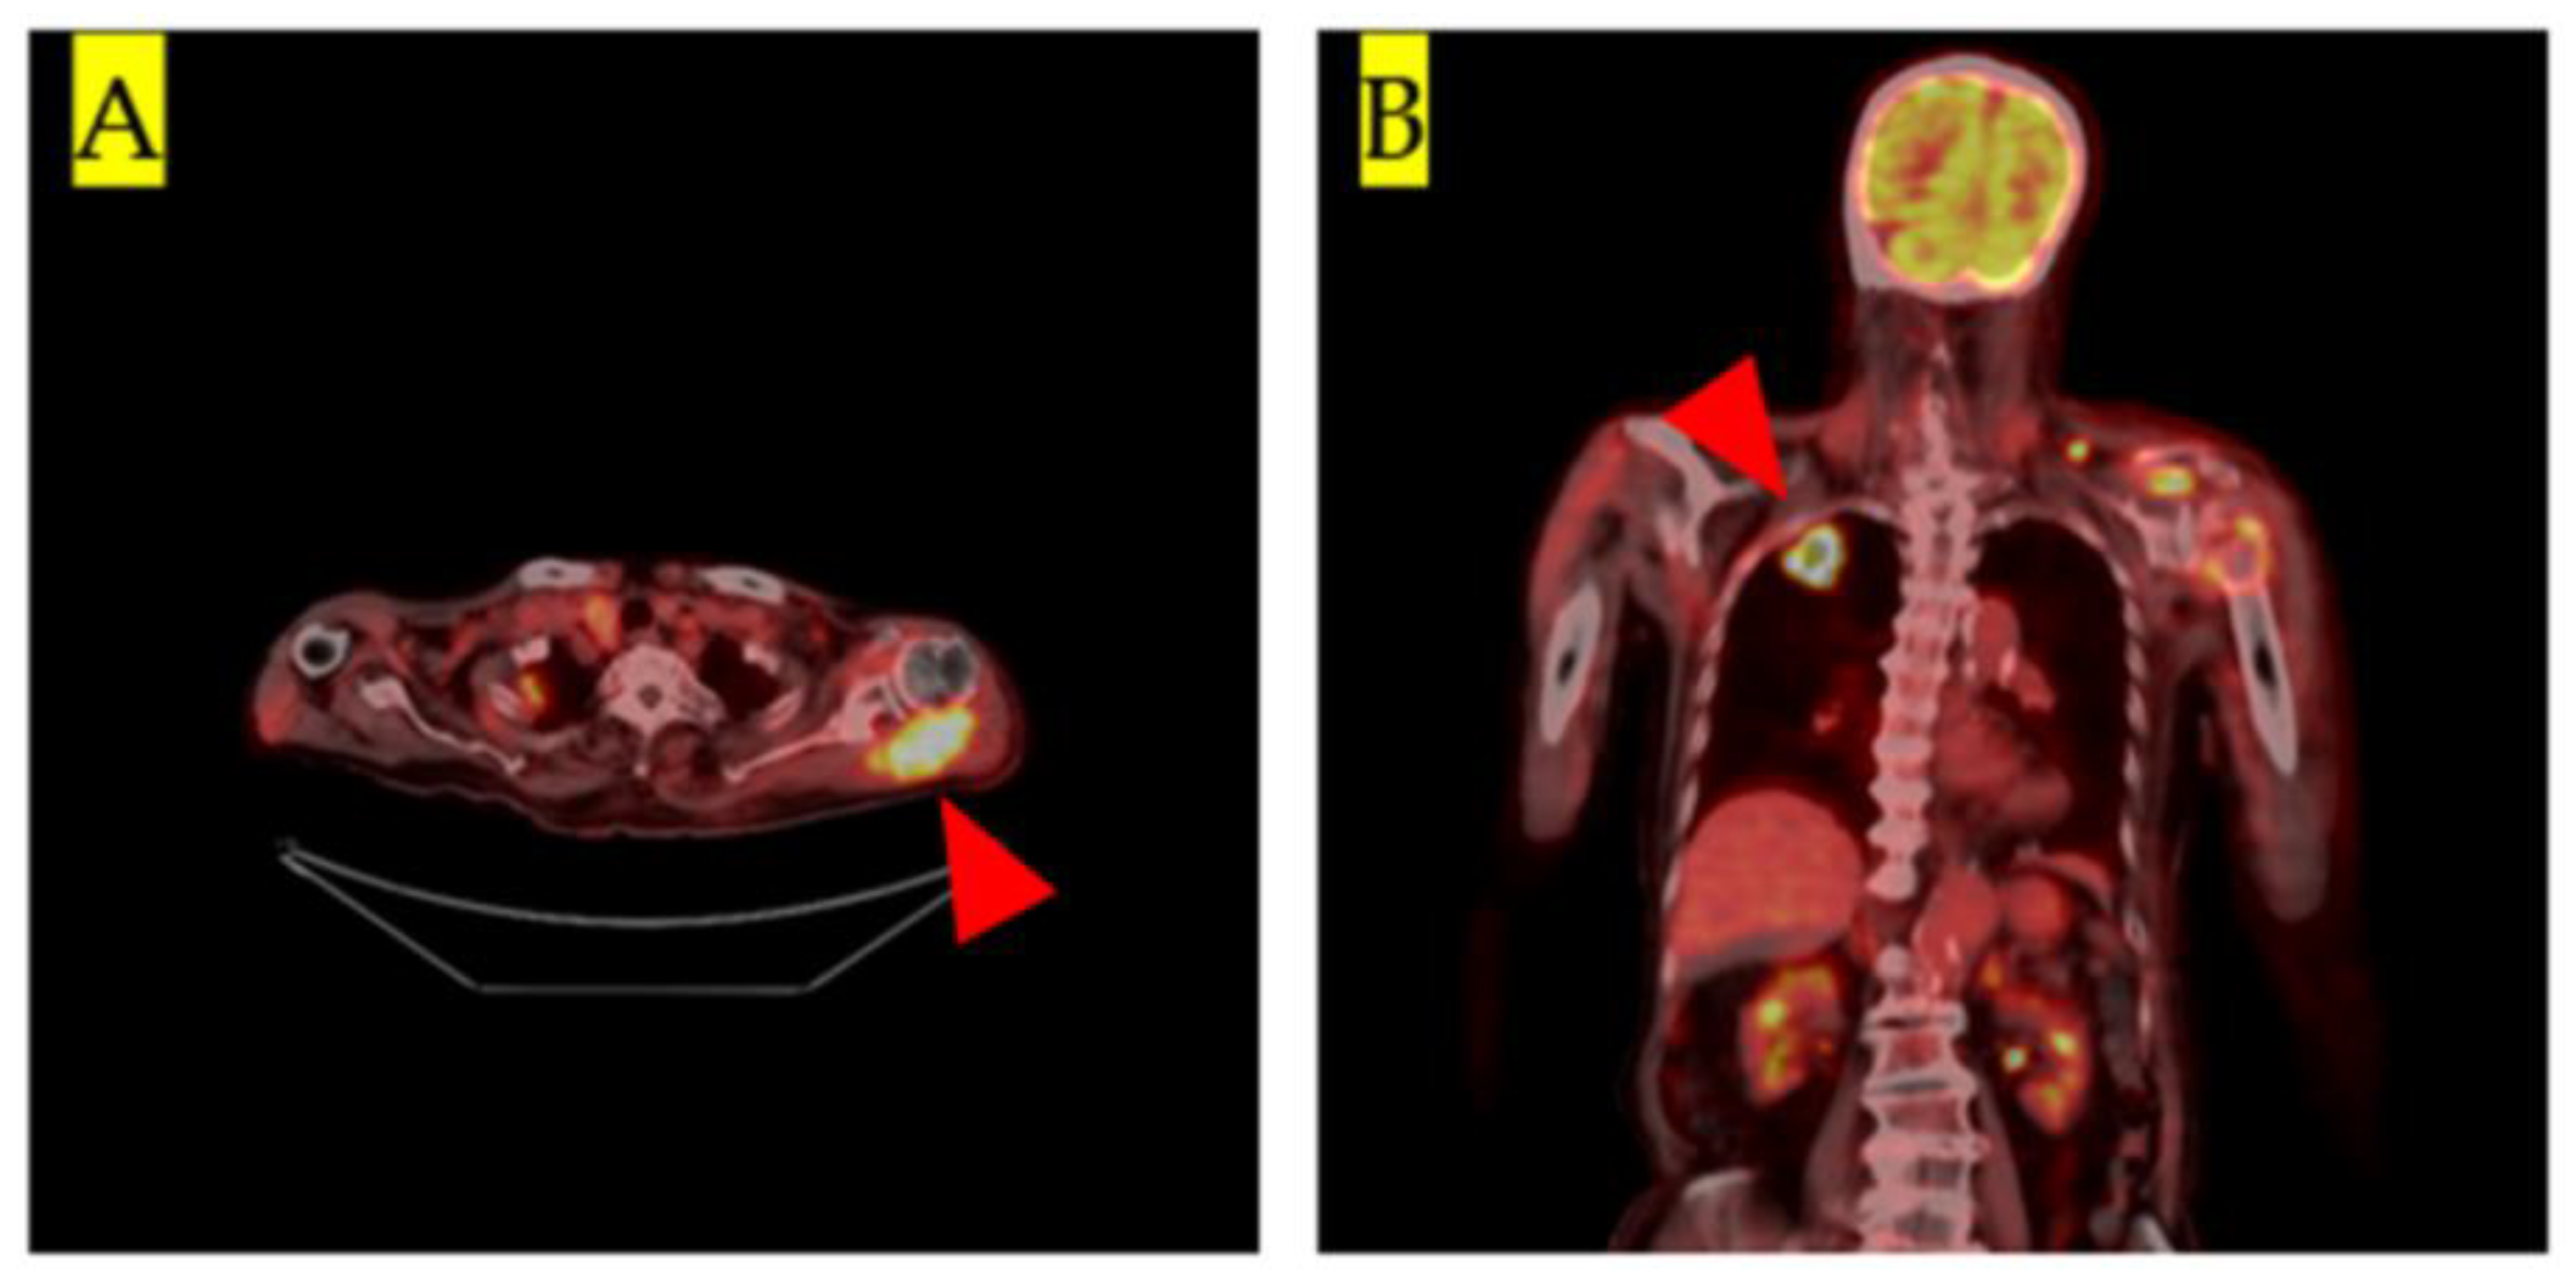

| Current case | 93 | 10 × 8 × 7 | Yes | Deep | MRI, PET-CT | Adenocarcinoma | Yes |